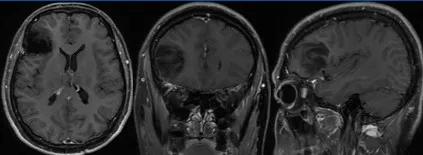

方法:颅脑 MRI(平扫 增强)

图像如下:

T2WI:

T1WI:

T2WI-FLAIR:

DWI:

ADC:

T1WI 增强轴位:

T1WI 增强矢状位:

T1WI 增强冠状位:

囊性脑膜瘤具有脑外肿瘤信号特征,具有明确占位效应; 囊性脑膜瘤的实质部分具备典型的脑膜瘤信号特点

形态: 呈类圆形、类椭圆形,形态规则,大小不等,少数呈分叶状,边界清楚

信号: 与病理类型有关,T1WI 呈等或稍低信号,与病理类型关系不明显,T2WI 纤维型呈稍高或等, 甚至低信号,上皮型、血管型、过渡型多呈高信号

囊腔可位于肿瘤内、边缘或外周脑组织内,呈大小不一圆形、类圆形、弧形等形态,T1WI 呈低信号,T2WI 呈高信号

增强扫描时,肿瘤实质部分强化明显,囊腔无强化,囊壁可有完整或部分环状强化。部分病例可出现典型硬脑膜尾征,有助于诊断